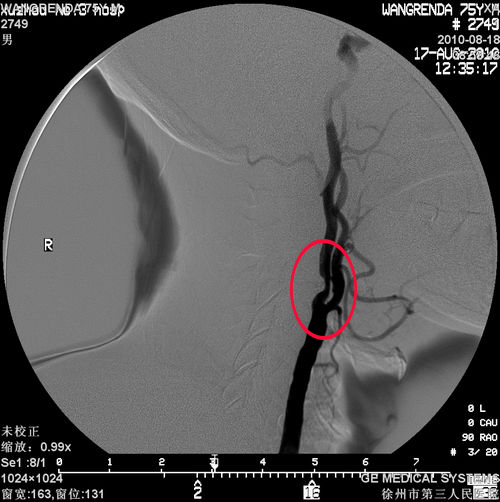

冠状动脉造影(2010-08-17)示:LAD近端局限重度狭窄;左肾动脉轻度狭窄;双颈内动脉狭窄(左侧95%)

左侧颈内动脉